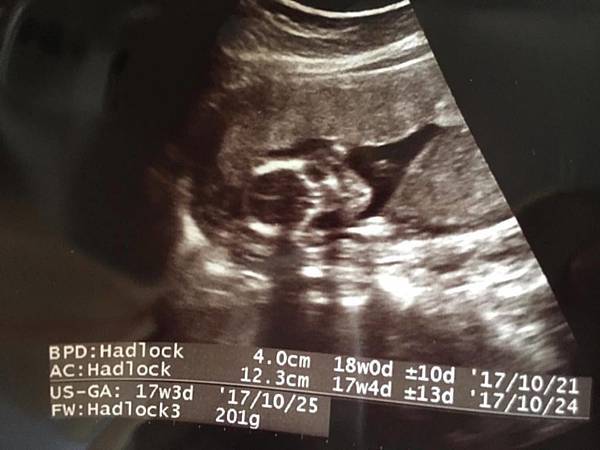

第十八周:

例行性產檢~這次醫生說他的一台超音波解析度比較好的壞掉了, 所以這次的照片跟之前比~就比較模糊 >"<但是小孩還是一樣很喜歡面對鏡頭!! 每次都會看到他的臉面對我們動來動去, 實在是超可愛!!!!